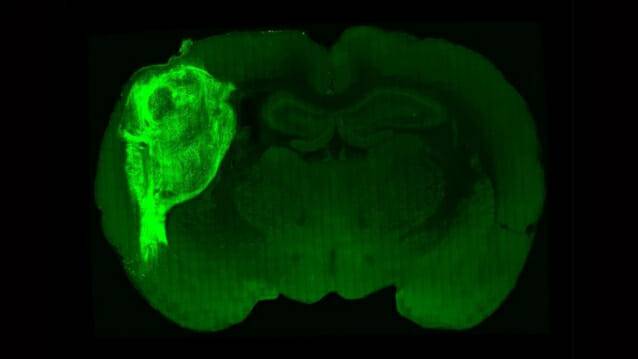

미국 스탠포드대 연구진은 인간 줄기세포로 만든 피질 오가노이드를 갓 태어난 쥐의 대뇌피질 중 체감각을 감지하는 부위에 삽입, 연구 결과를 12일(현지시간) 학술지 ‘네이처’에 공개했다. 이는 마치 "회로에 트랜지스터를 끼우듯" 성공적으로 작동했다고 연구진은 밝혔다.

연구진은 불이 켜질 때 수도꼭지를 핥으면 물이 나오게 해 쥐를 훈련시켰다. 이후 쥐의 뇌에 박은 광섬유로 인간-쥐 하이브리드 뇌에 빛을 비추자 쥐는 수도꼭지를 핥았다. 이는 인간 뇌 오가노이드가 쥐의 뇌와 잘 통합됐음을 보여준다.

또 연구진이 쥐의 수염을 만지자 사람 세포 부분이 신호를 내보냄도 확인했다. 사람 세포 부분이 감각을 수용하는 기능을 제대로 수행한다는 의미다.

반면, 자폐와 비슷한 증상을 보이는 티모시증후군 환자의 줄기세포로 만든 오가노이드는 쥐에 이식된 후 일반 오가노이드에 비해 작게 자랐고 기능도 미비했다.